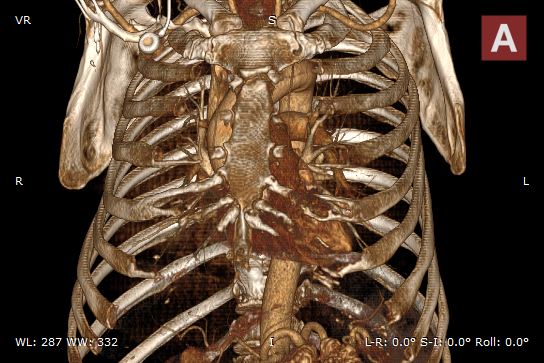

Bones and skin 1

Bones and skin 2

Bones and skin 3

Bones B/W